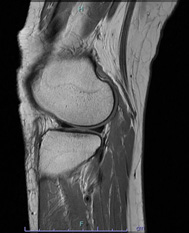

• 画像:正常な半月板MRI画像(右膝)

正常な半月板MRI画像(右膝)

• 画像:正常な半月板MRI画像(内側)

正常な半月板MRI画像(内側)

• 画像:正常な半月板MRI画像(外側)

正常な半月板MRI画像(外側)